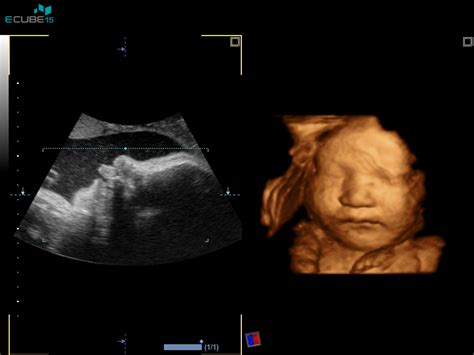

Deseti teden nosečnosti je tudi čas, ko se lahko odločite za različne diagnostične teste, ki bodo spremljali potek nosečnosti in zdravje vaših otrok. Ultrazvočni pregled v tem obdobju lahko že pokaže gestacijsko vrečko v maternici, pri vitalnih plodovih pa so vidni utripi srca.

Pomembna diagnostična metoda je merjenje nuhalne svetline, ki se običajno opravi med 10. in 14. tednom nosečnosti. Ta test pomaga oceniti tveganje za kromosomsko nepravilnost, kot je Downov sindrom. Od 10. tedna dalje je možno opraviti tudi Nifty test, ki je neinvazivna genetska preiskava. Za bolj zanesljivo ugotavljanje nepravilnosti pa je na voljo amniocenteza, ki se običajno izvaja med 15. in 20. tednom nosečnosti, zlasti v primeru genetskih obremenitev v družini ali slabih rezultatov drugih testov.

Zanesljiva potrditev večplodne nosečnosti je ultrazvočni pregled. Med zgodnjim ultrazvokom lahko ginekolog zazna prisotnost več kot enega ploda in več kot en srčni utrip, kar nedvoumno potrdi dvojno nosečnost. Vendar pa je včasih mogoče, da se en otrok na prvem ali drugem pregledu še ne vidi dobro ali se "skrije".